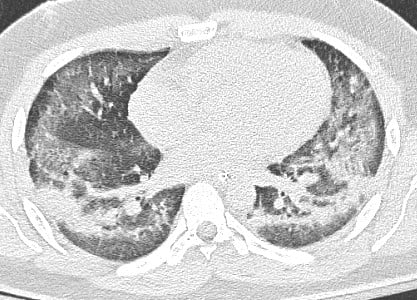

A 22 year-old male with a past medical history of moderate persistent asthma and anxiety disorder was found lying face down outside by his parents at home. Parents took him to primary care physician the next day and was prescribed 60 mg of prednisone. Patient showed worsening symptoms and presented to the emergency department with dyspnea and nonproductive cough the next day. Labs, imaging, and vitals revealed: WBC 12.8, temperature of 101.7 F, and chest x-ray showed increasing bilateral infiltrates. Patient was treated empirically for community-acquired pneumonia with ceftriaxone and azithromycin, and asthma exacerbation with prednisolone. Clinical worsening ensued, with the patient progressing from needing high flow nasal cannula to being intubated for hypoxic respiratory failure four days after onset of symptoms. Patient was transferred to a tertiary institution for suspected ARDS. On Day 1 of hospitalization, patient had coffee ground emesis on OGT suction 170ml, was put on pantoprazole 40mg po BID and closely monitored for upper gastrointestinal bleed/melena. On day 2 of hospitalization, chest CT showed diffuse bilateral ground glass opacities with peripheral sparing in all lobes of both lungs (Figure 1). Respiratory viral panel and urine legionella Ag screening were negative. Procalcitonin was within normal limits. Laboratory results were significant for a white blood cell count of 16.7. Antibiotic coverage was increased to vancomycin/piperacillin and tazobactam due to the development of a low-grade fever on day 4 of hospitalization. Bronchial alveolar lavage from right upper and middle lobe on day 4 of hospitalization was negative for malignant cells, thin prep slide showed few alveolar macrophages and benign bronchial epithelial and squamous cells.

Figure 1. CT scan showing diffuse bilateral ground glass opacities with peripheral sparing in all lobes of both lungs